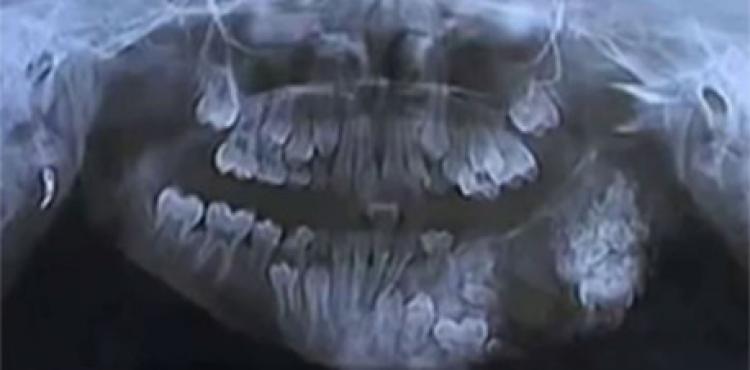

خلع 80 سنا لدى طفل هندي عمره 7 أعوام